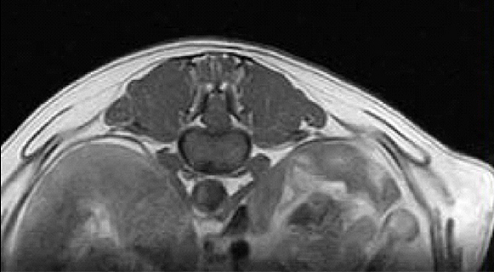

【画像診断】~ダックスフンド、雄10歳、グレート3の椎間板ヘルニア~

▲椎間板ヘルニアがあるMRI像T13-L1の頭側像、造影後のT1強調画像(キャミックに依頼)

▲椎間板ヘルニアがあるMRI像、T13-L1の尾側像、造影後のT1強調画像(キャミックに依頼)